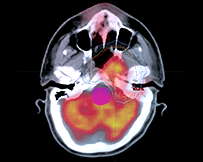

影像引導(dǎo)放射治療(IGRT)

IGRT是一種四維放射治療技術(shù),它在三維放療技術(shù)的基礎(chǔ)上加入了時(shí)間因數(shù)的概念,充分考慮了解剖組織在治療過程中的運(yùn)動(dòng)和分次治療間的位移誤差,在患者進(jìn)行治療過程中利用影像設(shè)備對腫瘤及正常器官進(jìn)行實(shí)時(shí)監(jiān)控,并根據(jù)器官位置的變化調(diào)整治療條件,使照射野緊緊“追隨”靶區(qū),使之能做到真正意義上的精確治療。